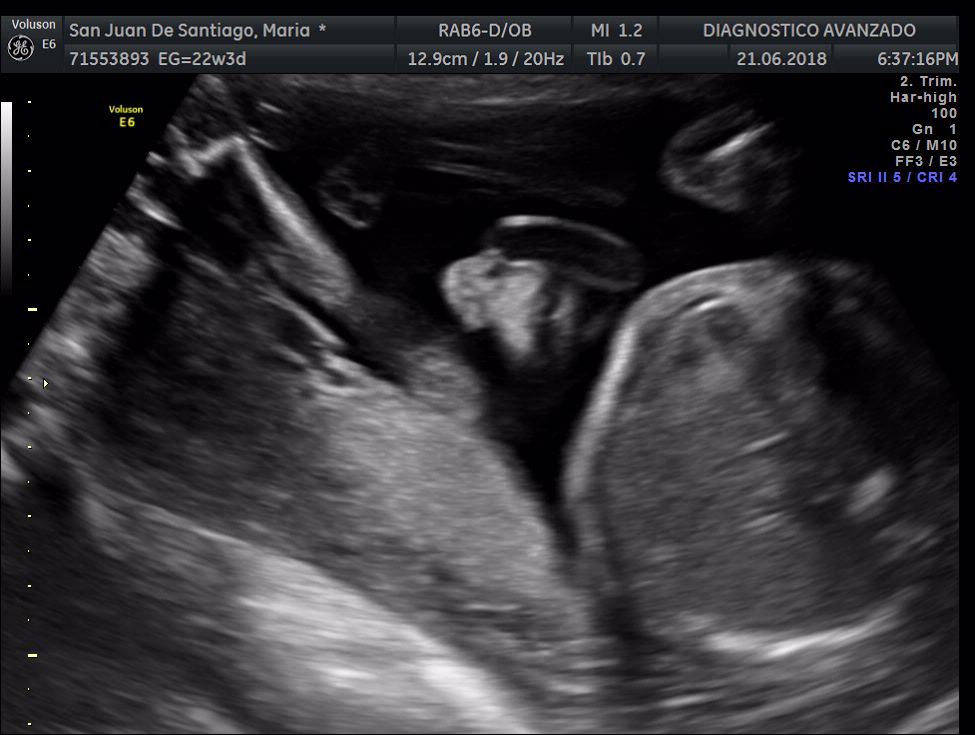

¡Hola a todos! Hoy hemos ido a hacer la tradicional ecografía 3D de la niña, os dejamos todo el material (aunque es un poco demasiado).